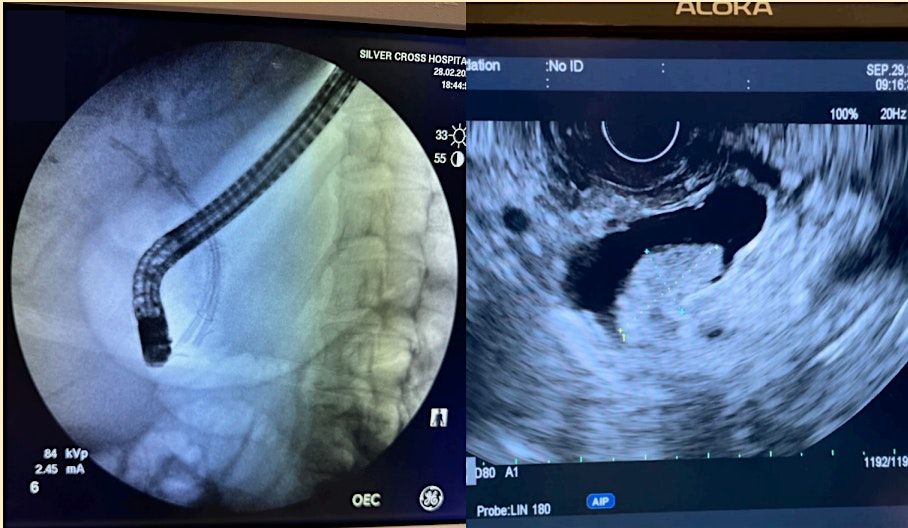

Welcome to the Gastroenterology and Endoscopy event for Doctors, Nurses, and Associates! Join us for a day of learning and networking at The Doubletree Hotel Chicago-Oak Brook, located at 1909 Spring Road, Oak Brook, IL. This in-person event will feature expert speakers, hands-on workshops, and the latest advancements in the field. Don't miss this opportunity to enhance your knowledge and connect with colleagues in the industry. Register now to secure your spot!

Day 2 will be held at Silver Cross Hospital 1890 Silver Cross Blvd.New Lenox, IL 60451.